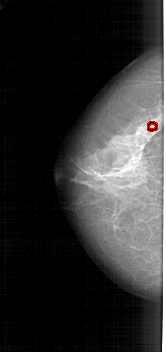

A_1946_1.LEFT_CC

LEFT_CC LINES 4921 PIXELS_PER_LINE 2311 BITS_PER_PIXEL 12 RESOLUTION 43.5 OVERLAY

FILE: A_1946_1.LEFT_CC.OVERLAY

TOTAL_ABNORMALITIES 1

ABNORMALITY 1

LESION_TYPE CALCIFICATION TYPE PLEOMORPHIC DISTRIBUTION CLUSTERED

ASSESSMENT 4

SUBTLETY 3

PATHOLOGY BENIGN

TOTAL_OUTLINES 2

BOUNDARY